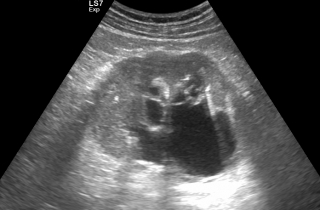

Kamica nerkowa

Kamica to jedno z częstszych schorzeń układu moczowego. Kamień, który wydostanie się z nerki i utknie w moczowodzie blokuje odpływ moczu powodując tzw. wodonercze oraz kolkę nerkową. W #KlinikaBulwarDedala leczymy kolki nerkowe.